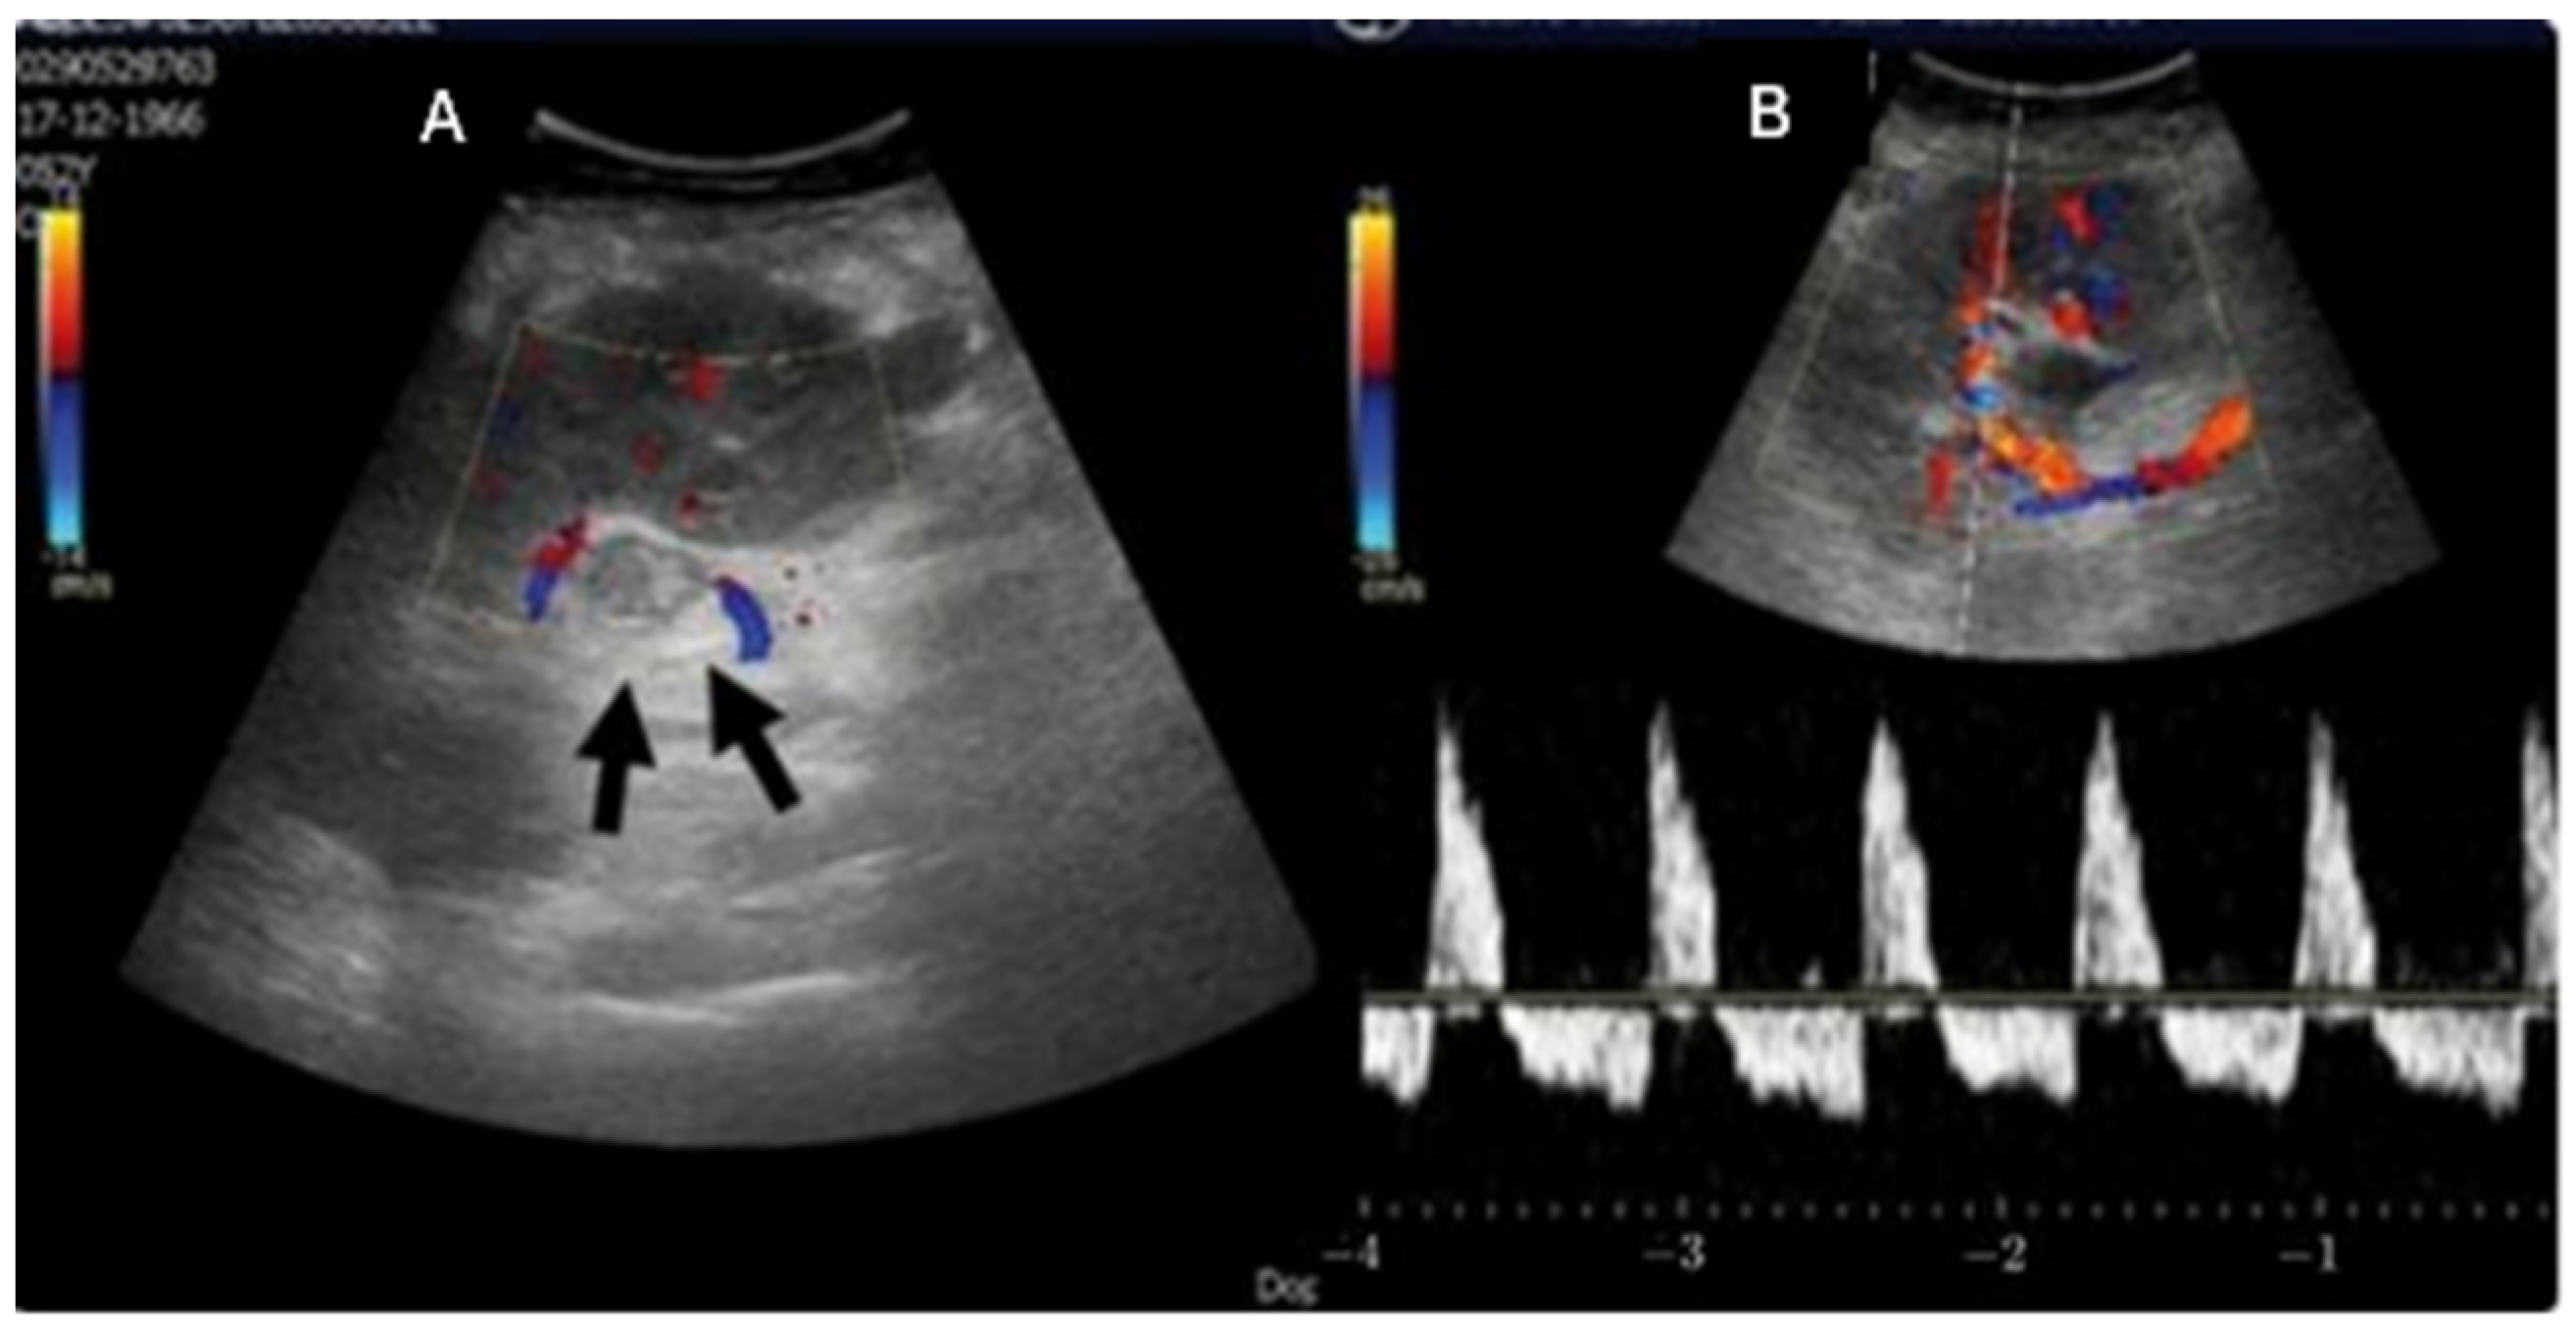

Arterial Stenosis

- Franke, D. The diagnostic value of Doppler ultrasonography after pediatric kidney transplantation. Pediatr. Nephrol. 2022, 37, 1511–1522. [Google Scholar] [CrossRef]

- Ghirardo, G.; De Franceschi, M.; Vidal, E.; Vidoni, A.; Ramondo, G.; Benetti, E.; Motta, R.; Ferraro, A.; Zanon, G.F.; Miotto, D.; et al. Transplant renal artery stenosis in children: Risk factors and outcome after endovascular treatment. Pediatr. Nephrol. 2014, 29, 461–467. [Google Scholar] [CrossRef]